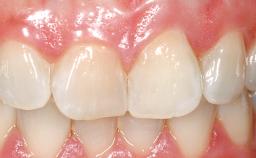

A 30-year-old female patient had lost tooth 21 and was referred to our clinic for consultation and treatment. Due to advanced apical infection, tooth 21 had been extracted two months earlier at another clinic and an acrylic-resin tooth had been bonded to the adjacent teeth. The patient desired implant treatment to avoid any damage to the adjacent natural teeth. While the patient had no history of any systemic disorder, she was a heavy smoker and exhibited medium to advanced periodontitis in the entire jaw. After the initial treatment to achieve a pocket probing depth of less than 4 mm and no bleeding on probing, a decrease in the height of the papillae mesial and distal to the extraction site and overall gingival recession were observed.

Prosthesis Type FDP

Retention Cemented, with meso-structure Cemented, with meso-structure

Provisional Implant-Supported Prosthesis Prosthodontic margin < 3 mm apical to mucosal margin Prosthodontic margin < 3 mm apical to mucosal margin

Soft Tissue Contour and Volume Slightly compromised